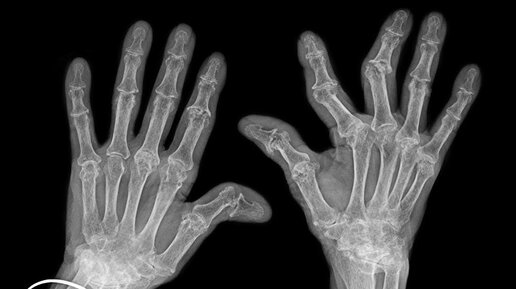

Все мы считаем, будто хруст пальцами приводит к тому, что хрящи изнашиваются, истираются и утончаются. И хотя действительно есть факторы, которые могут привести к артриту – к примеру, травмы, хруст пальцами не является одним из них. Ученые установили, что остеоартрит – это результат повторяющихся движений и приложения силы, а не хруста пальцами. Хруст суставов к артриту и артрозу действительно имеет отношение, но он является следствием, а не причиной! Кости не имеют никакого отношения к хрусту....

Как часто вы слышали, что хрустеть пальцами вредно? Чаще всего в качестве аргумента приводится повышенный риск артрита и болезней суставов, возникающий из-за хруста. Но так ли это на самом деле? Вредно ли щелкать суставами и почему? Как отучиться от этой привычки? Разбираемся в вопросах вместе с медицинским автором раздела «‎Здоровье» на Sports.ru, врачом-терапевтом Александром Шестаковым. Почему хрустят суставы? Сустав – это место соединения двух или более костей, которое обеспечивает их движение друг относительно друга...